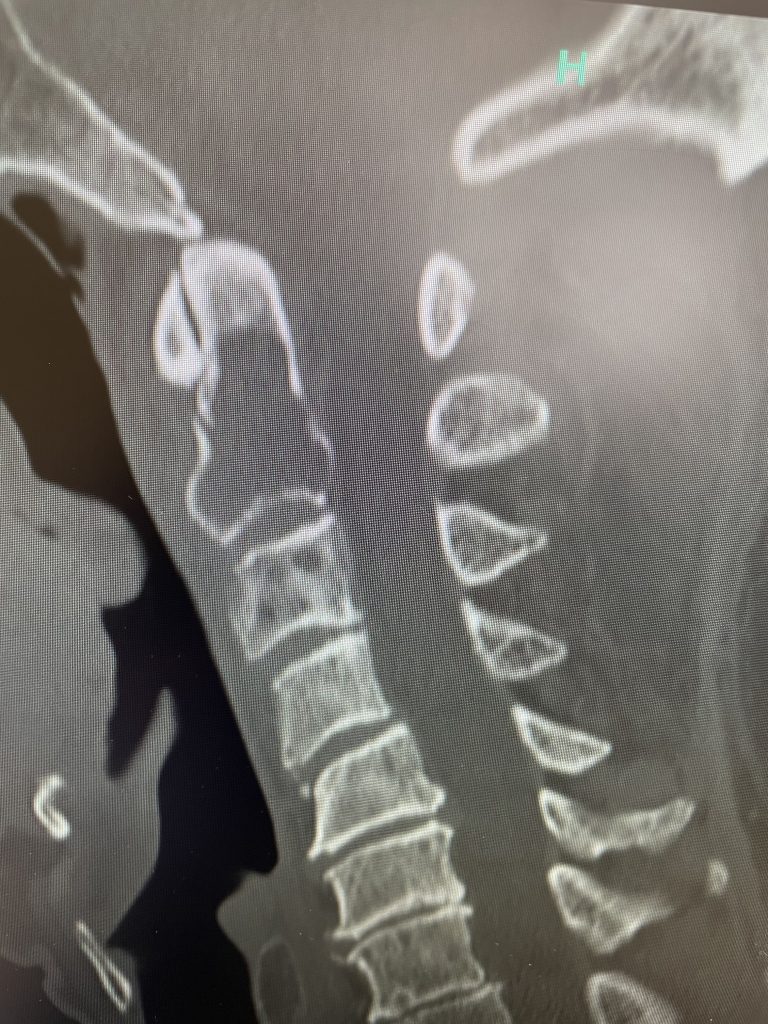

Fig 1: Sagittal and axial CT scan showing a lyric C2 lesion with extension into the posterior elements on the right side

Here is a tough case: This is a 72 year-old male who presented with several months of progressive neck pain without symptoms of the arms or legs. He had a history of prostate cancer for which he was treated. He had a biopsy of a hip lesion which was consistent with Paget’s disease, a benign but aggressive disease of the bone. He had imaging studies that were consistent with a destructive lytic C2 bony vertebral body lesion with extension into the posterior bony ring and possibly affecting C3 vertebral body (Fig 1). The patient’s urologist didn’t believe the patient had metastatic prostate cancer since his PSA was not elevated. The lesion itself was also not consistent with metastatic prostate cancer as they are usually blastic or bone forming lesions not bone destroying. His oncologist had initially sent us the patient with the thought that this was Pagets’s disease. Paget’s disease rarely affects the cervical spine and the bony appearance is more heterogeneous with a “picture-frame” appearance and hyperdense and not lytic. The patient underwent a PET scan which was “hot” consistent with malignant tumor. The patient underwent a bone marrow biopsy and had blood work consistent with a multiple myeloma diagnosis. The patient underwent radiation treatment with 25 fractionated cycles. The patient was given one percocet to control his pain by his oncologist.